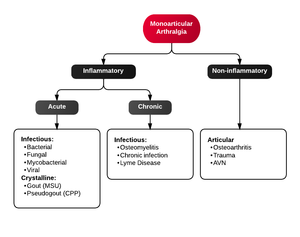

Differential Diagnosis

Monoarticular arthritis

- Acute osteoarthritis

- Avascular necrosis

- Crystal-induced (Gout, Pseudogout)

- Gonococcal septic arthritis

- Nongonococcal septic arthritis

- Lyme disease

- Malignancy

- Reactive poststreptococcal arthritis

- Trauma-induced arthritis